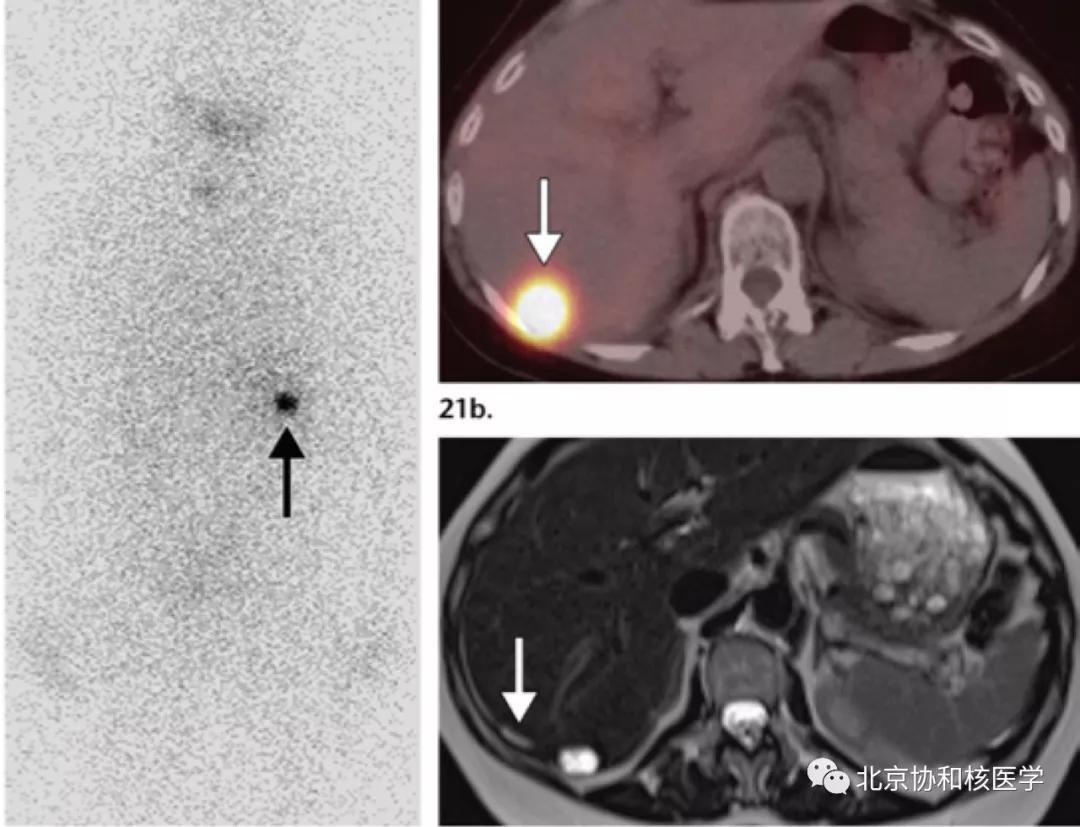

39岁女性,恶性卵巢甲状腺肿病史,行右侧卵巢切除术、甲状腺切除术、碘131治疗,碘扫可见残余甲状腺摄取、盆腔转移灶摄取及肝转移灶摄取:

鼻骨骨样骨瘤所致碘摄取,腹部另可见由于巨大肾囊肿所致碘异常摄取: